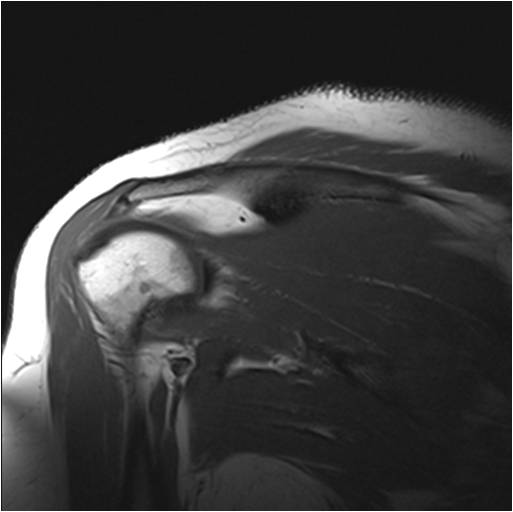

Glenohumeral Joint and Quadrangular Space

Identify: Teres minor, long head triceps, surgical neck humerus, teres major. Axillary nerve, head humerus, glenoid fossa, deltoid, supraspinatus, acromion.